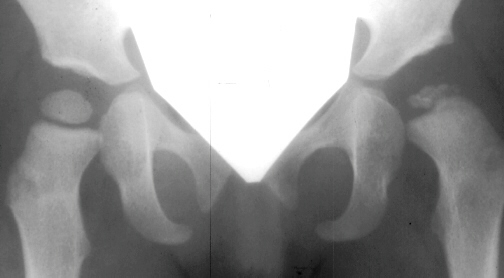

The progression of the hip is documented by x-rays taken at 1 year of age, 2 years of age, 3 years of

age, 5 years of age, 7 years of age, then at ten years of age, early closure of the lateral portion of proximal growth plate observed. Coxa valga was also observed.

The initial changes in the ossific center may follow exactly those seen in Group I, but in addition there is damage to the lateral part of the physis. The early roentgenographic signs indicating lateral physeal damage are: (1) lateral ossification, (2) lateral physeal irregularity and bridging, (3) lateral notching of the epiphysis, and (4) a lateral metaphyseal defect. The damage to the physis may remain dormant. By the age of ten years, however, valgus deformity of the head on the neck develops.( This type occurred in 35% of total AVN at AIDI.)